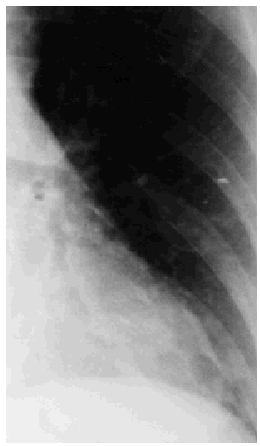

Following diagnosis of iron-deficiency anemia a barium enema examination was carried out and the contrast medium was accidentally administered into the vagina, which tore at the side. The fluoroscopy showed venous intravasation of barium. The examination was discontinued and a chest x-ray revealed pulmonary barium embolization (Figure). The patient complained of dizziness and had signs of hypotension and shivering, followed by fever of 38ºC. The symptoms abated after administration of intravenous antibiotics and the vaginal tear was repaired surgically. The results of analysis at this time were prothrombin time 100%; activated partial thromboplastin time 30/30 s; fibrinogen, 2.56 g/L; positive for fibrinogen degradation products (80 µg/mL); platelets, 149x109/L. Tests for barium in the blood and urine were negative.

Figure. Amplified image showing a barium particle in greater detail.

Although soluble barium salts are absorbed by the digestive tract and enter the circulatory system producing hypokalemia, cardiac arrythmia,2,3 and renal failure,4 barium sulfate is not absorbable or soluble and does not have such toxic effects. When barium reaches the lungs it can cause a clinical picture of pulmonary embolism with dyspnea, tachypnea, cough, or acute pulmonary edema. Barium can be detected in the liver and the lungs by simple x-ray and also by computed tomography.5 The mortality rate for this condition is high: of the 17 cases we reviewed in the literature, 10 ended in death. The condition was more serious when systemic circulation was affected, with death occurring in 8 patients out of 11, as opposed to 1 patient out of 6 when portal circulation was affected. The mortality rate may also have depended on the quantity of barium particles involved, as in surviving patients the amount of barium that entered the circulatory system was less than 5 mL.5,6 In surviving patients barium can be detected in images of the affected organs up to several months later, even when the patient feels well. In the case we describe barium was still being detected on chest x-rays some 7 months after the accident although the particles were smaller and had decreased in number; one of them even seemed to be forming a granuloma.